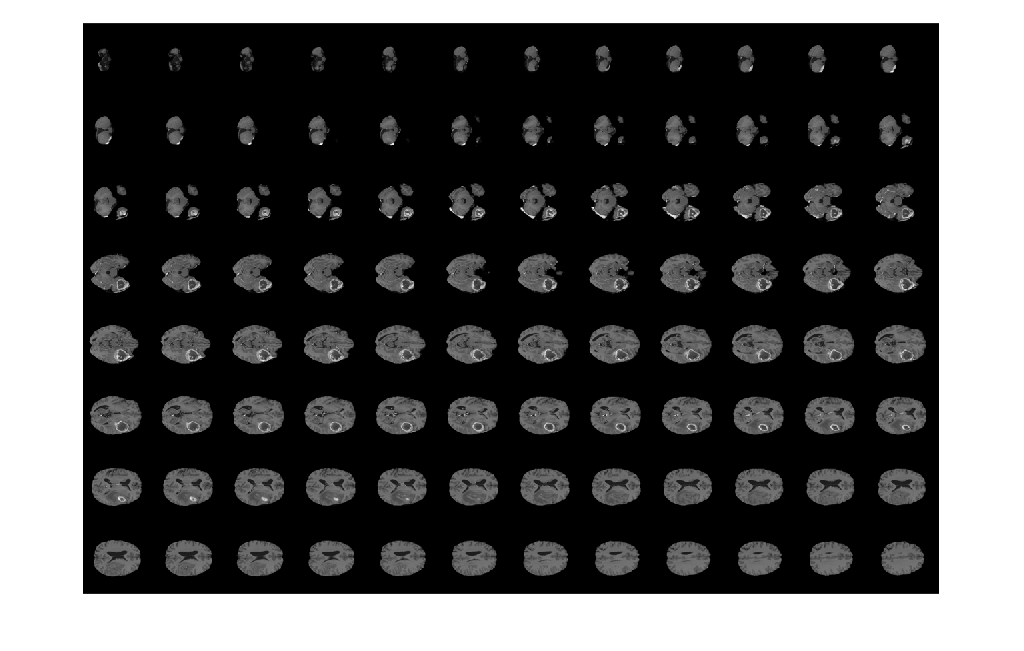

Display horizontal slices of the data by using the montage function.

montage(V,map,'Size',[3 9]);